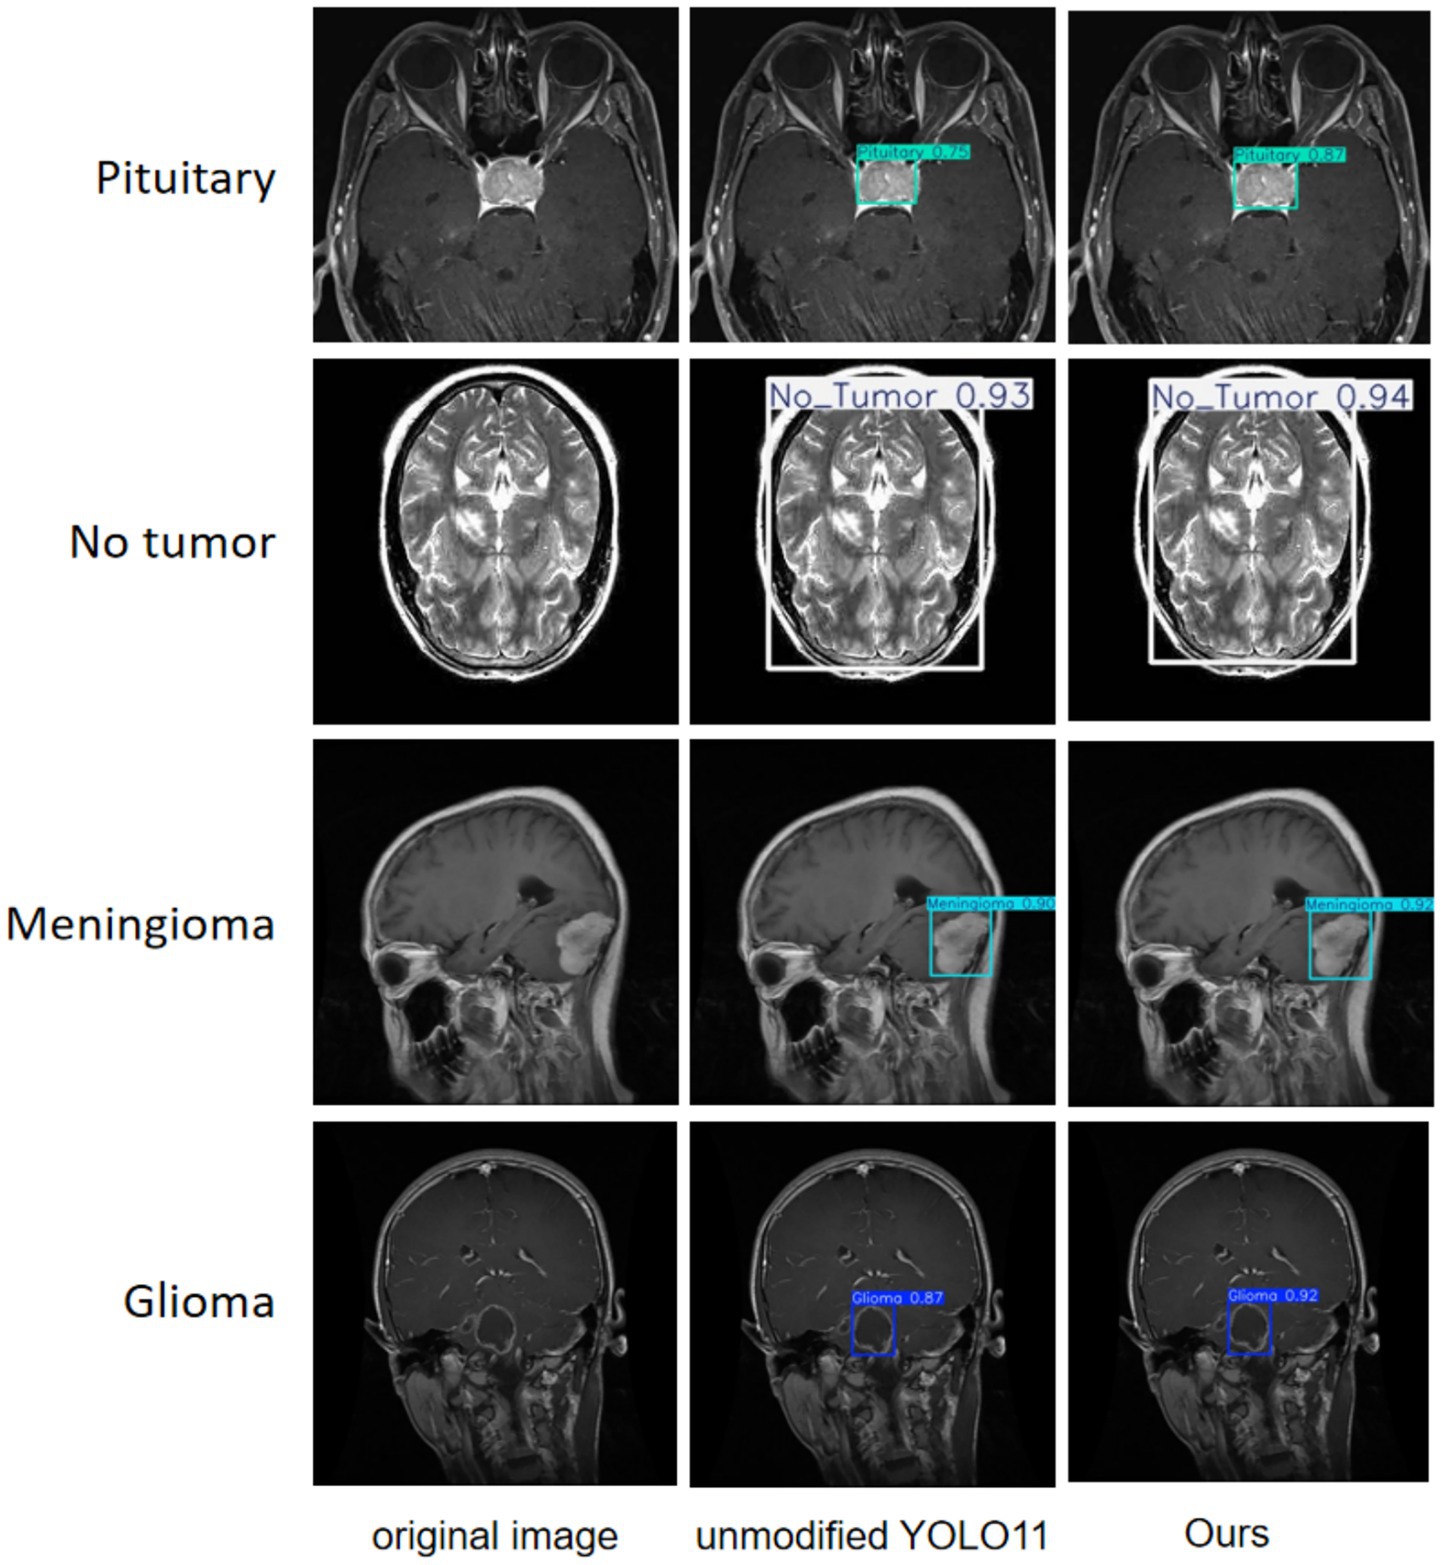

A more intuitive view of the effects before and after the improvement can be seen in the original and detection result plots randomly selected from the internal and external test sets, see Figures 13, 14. Each line compares the effects of a brain tumor type before and after detection and before and after the model improvement, with the original plot, the original YOLO11n detection result plot, and the improved YOLO11n detection result plot, in order from left to right. The text on the left side above the target box in the detection result plots is the brain tumor type, and the number on the right side is the detection confidence level. Column 3 of both Figures 13, 14 show that the improved model can detect gliomas, meningiomas, pituitary tumors, and no tumors (entire brain region) with high confidence. Table 5 shows the quantitative results of the detection performance for various categories of the improved model in the external test set.

Figure 13. Classification detection results of YOLO model before and after improvement on internal test set.